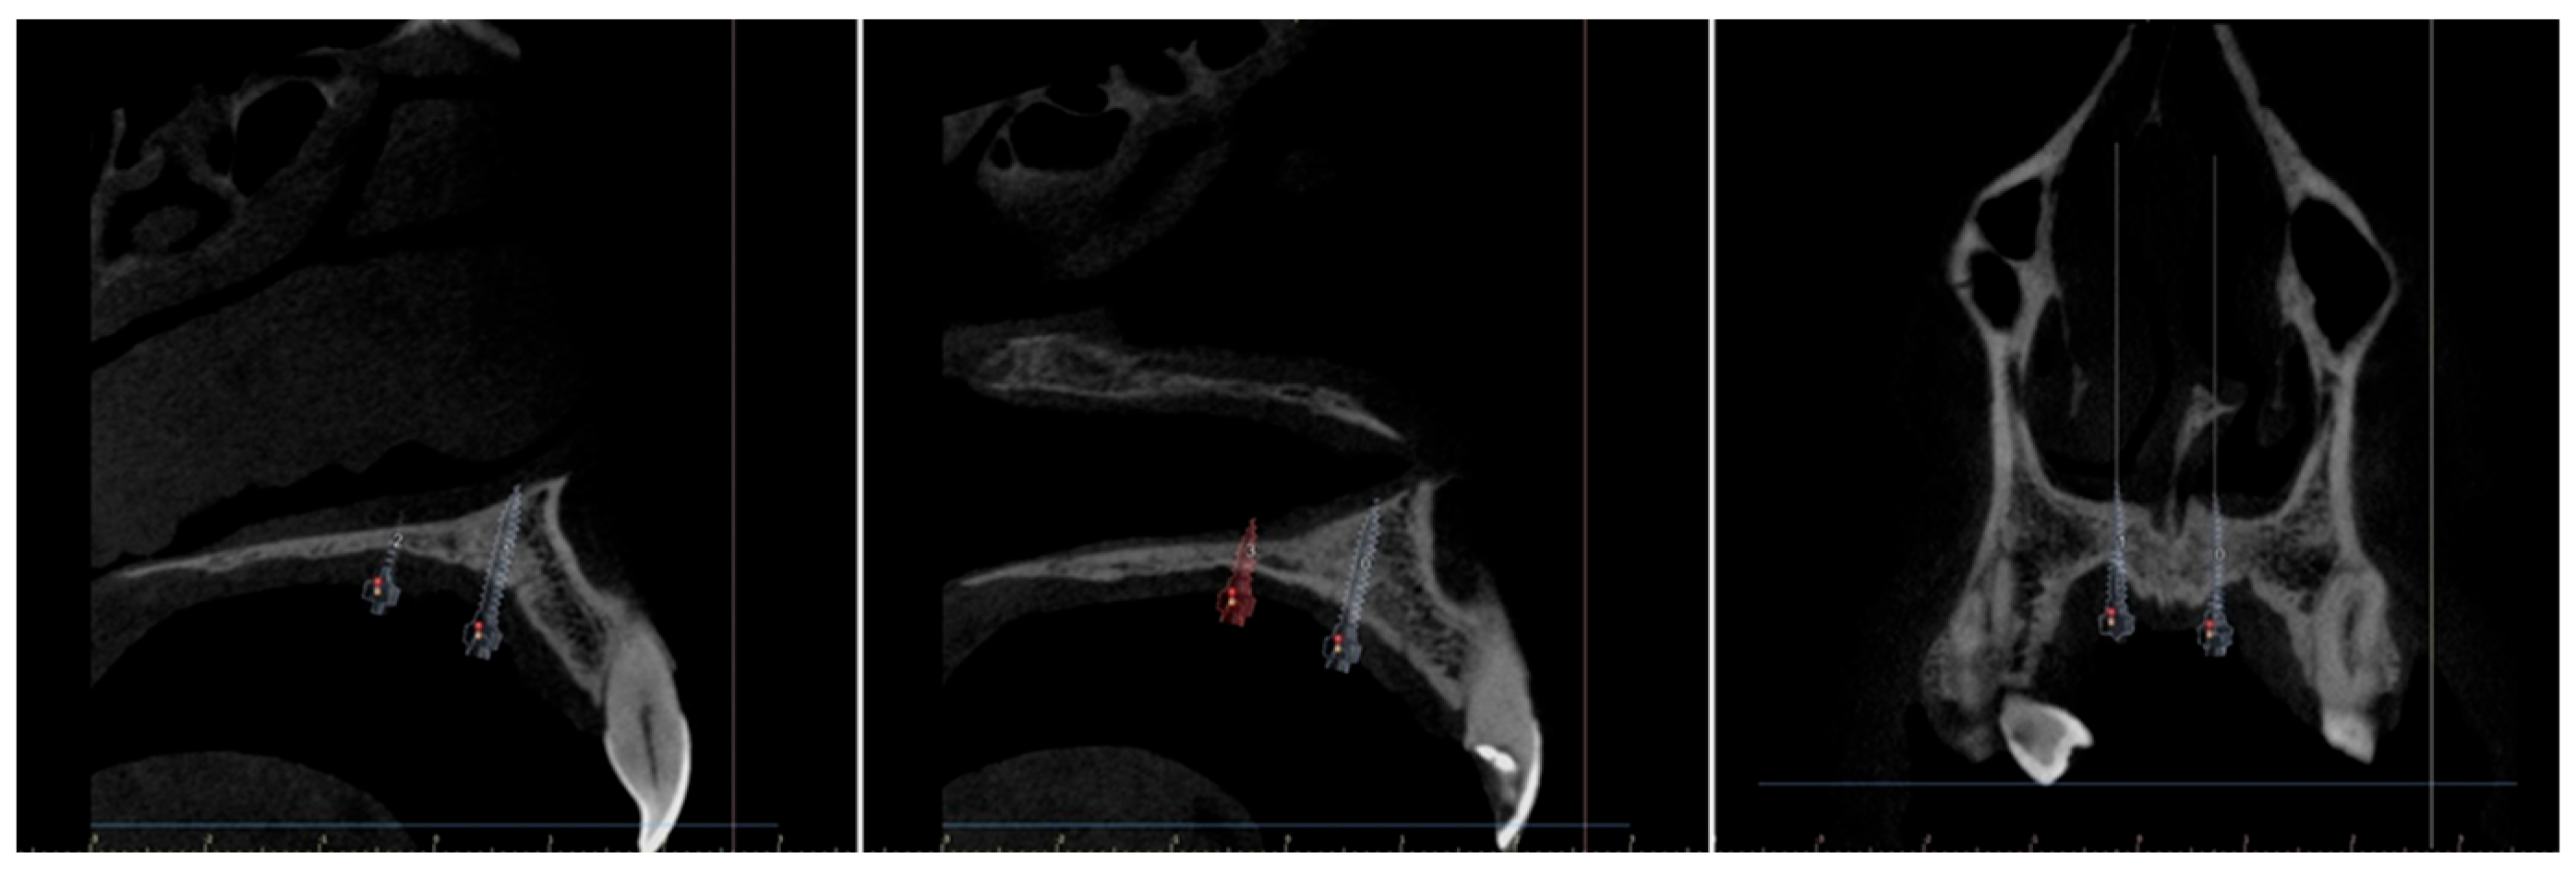

- The MSE system designed by Dr. Won Moon (Biomaterials Korea, Seoul, Republic of Korea) that has a jackscrew component with four parallel holes for mini-implant insertion and supporting arms on both sides soldered to the molar bands, aiming to stabilize the device’s position during expansion. Regularly, the position of the appliance is between the two zygomatic-maxillary buttresses, frequently located at the level of the first molars, so the mini screws are located just anteriorly to the soft palate [10,28]. An example of the posterior positioning of the MSE jackscrew with four mini-implants performed for a patient in our clinic, can be seen in Figure 2.